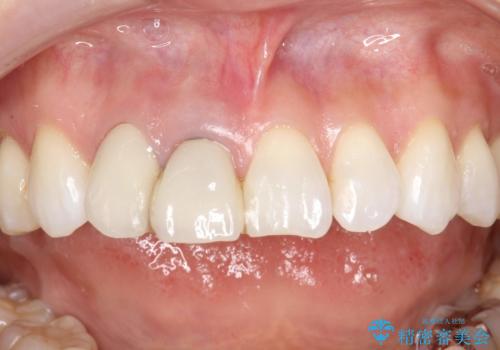

前歯がぐらぐらする 抜歯→ブリッジへ

古いかぶせ物は土台ごと歯から脱落してしまっており、歯の内面には複数の亀裂が入っている状態でした。残存歯質が非箔であることと、動揺の程度から、やむを得ず抜歯→ブリッジという方法を選択していただき、歯根挺出を用いることでなるべく前歯の骨の陥没を防ぎ、ブリッジを製作しました。

かぶせ物の種類:PFZ standard